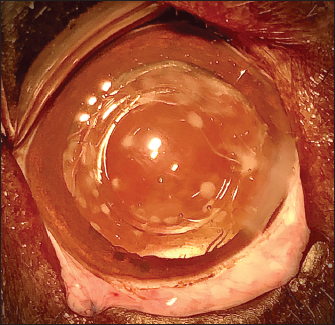

Fig. 2. Three cases of marked PCO (increasing intensity from left to right) obstructing the visual axis (intraoperative view).

After 3.2-mm clear corneal incision using an angled microsurgical knife (Unique Technologies, Inc, Mohnton, USA) and inflation of the anterior chamber with 1.6% sodium hyaluronate viscoelastic substance (Ophteis Bio 1.6, Rayner, Worthing, UK), anterior capsulorhexis was performed. Then conventional phacoemulsification (Infiniti Vision System, Alcon Laboratories, Inc. Fort Worth, USA) using a one-handed technique was completed, followed by meticulous irrigation-aspiration of the residual cortical material and polishing of the posterior capsule (PC). At this stage, a marked PCO obstructing the visual axis was found in five cases (Fig. 2), previously diagnosed by ultrasound in the sixth. In order to restore the transparency of the visual axis, an axial posterior capsulorhexis (APC) was performed in all cases, before or after implantation of an IOL (Intraocular implant PFI, Medicontur, Zsambék, Hungary). The IOL implantation inside the capsular bag was performed in a conventional manner using an injection cartridge through the limbal keratotomy. For the four cases implanted before APC, the approach of the PC was to inject viscoelastic gel into the capsular bag to mobilize the IOL (inside the bag) to access the PC, using two variations. The first method was to push and position the IOL laterally and obliquely toward the equator of the bag by gently injecting the viscoelastic gel, to reach the central area of the PC for the surgical approach (Fig. 3). A second method was to leave the IOL centered in the bag and inject the viscoelastic gel between the IOL and the PC, allowing visualization of the PC through IOL optic for its surgical approach under it. In all cases, the amount of gel injected was visually controlled by the degree of concave swelling of the PC to avoid overinflating it.